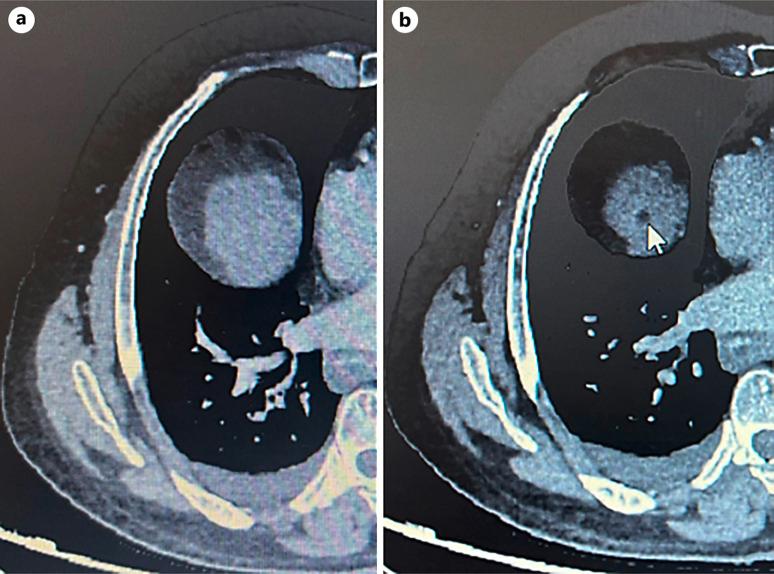

A 63-year-old male with compensated hepatitis B-related cirrhosis was under routine surveillance when a suspicious liver lesion was detected on ultrasound. Subsequent contrast-enhanced computed tomography (CT) confirmed the presence of an 18-mm HCC in segment VIII, corresponding to Barcelona Clinical Liver Cancer stage A. Due to limited curative treatment options, transarterial chemoembolization was considered. However, a follow-up CT scan was performed 2 weeks before the procedure unexpectedly revealed complete regression of arterial enhancement, suggestive of spontaneous tumor necrosis. The patient remained asymptomatic, with stable liver function and mild biological inflammatory markers. No evidence of vascular thrombosis or significant systemic inflammation was noted, suggesting localized vascular disturbances or intrinsic tumor factors might have precipitated the necrosis.

一名63岁的男性,患有代偿性乙型肝炎相关肝硬化,在常规监测期间,超声检查发现肝脏有可疑病变。随后的对比增强计算机断层扫描(CT)证实肝VIII段存在一个18毫米的HCC,符合巴塞罗那临床肝癌分期A期。由于根治性治疗选择有限,考虑进行经动脉化疗栓塞术。然而,在手术前2周进行的一次随访CT扫描意外显示动脉强化完全消退,提示肿瘤自发性坏死。患者仍无症状,肝功能稳定,生物炎症指标轻度升高。未发现血管血栓形成或明显全身炎症的证据,提示局部血管紊乱或肿瘤内在因素可能促成了坏死。